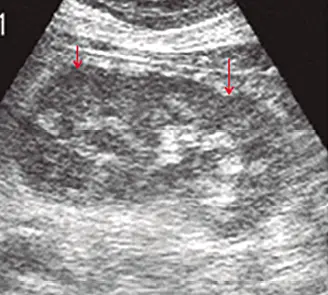

Otro punto a tener en cuenta es la trama o tipo de grano, este puede ser fino homogéneo (parénquima renal – testicular) que indica trama normal o ser grueso, heterogéneo: trama anormal (insuficiencia renal crónica). Fig: 16 a, b.

Fig: 16–a

Fig: 16–a, corte longitudinal que muestra un riñón derecho, el cual presenta un parénquima con ecos finos, homogéneos.

Fig: 16–b

Fig: 16–b, corte longitudinal de riñón izquierdo: parénquima con aspecto de grano grueso, heterogéneo. Esto puede indicar daño renal; el cual debe ser correlacionado con el laboratorio.